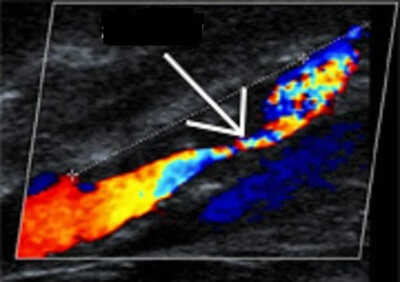

Μία απλή εξέταση γιά την διάγνωση της καρωτιδικής νόσου είναι το έγχρωμο doppler υπερηχογράφημα (triplex) των αγγείων του τραχήλου. Η ακρίβεια των αποτελεσμάτων της εξετάσεως αυτής εξαρτώνται από τον ιατρό που διενεργεί την εξέταση, ωστόσο στις περισσότερες περιπτώσεις είναι εφικτή η ασφαλής επιβεβαίωση της απουσίας σημαντικής καρωτιδικής νόσου. Ο ακτινολόγος ή εξειδικευμένος νευρολόγος που διενεργεί την εξέταση πρέπει να είναι έμπειρος και σε περίπτωση αμφιβολίας, να ζητείται επιβεβαίωση των αποτελεσμάτων με ψηφιακή αγγεογραφία.

- Το υπερηχογράφημα είναι πολύ χρήσιμο εργαλείο γιά την εκτίμηση του βαθμού της στενώσεως και της μορφολογίας της καρωτιδικής πλάκας. Σε B-mode brightness ανάλογα με τον βαθμό της ηχογένειας (GSM, gray scale median score) καθορίζεται η ετρογένεια της πλάκας και διακρίνονται 4 τύποι (κριτήρια κατά Gray-Weale et al). Χαμηλό GSM score σχετίζεται με υψηλή περιεκτικότητα σε λιπίδια και αιμορραγία μέσα στο νεκρωτικό πυρήνα της πλάκας, άρα ασταθή πλάκα. Με χρησιμοποίηση σκιαγραφικού (μικρο-φυσσαλίδες) μπορεί να δεί κανείς νεο-αγγείωση της πλάκας. Επαναλαμβάνουμε ότι τα αποτελέσματα της εξετάσεως αυτής εξαρτώνται από τον ιατρό που διενεργεί την εξέταση και ότι μπορεί να δώσει συχνά ψευδώς θετικά αποτελέσματα.